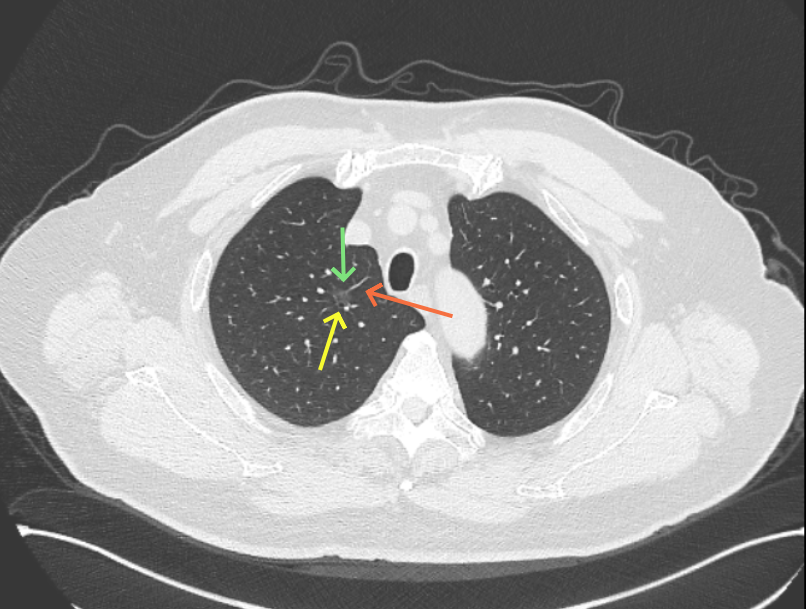

微小血管走向病灶,磨玻璃的密度淡而较纯。

其他主要病灶情况:

左上叶舌段结节,也是磨玻璃密度,轮廓与边界清。